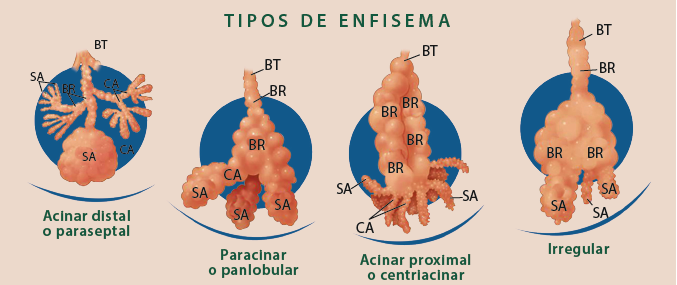

Los 2 fenotipos más conocidos de la EPOC son la bronquitis obstructiva crónica y el enfisema. La bronquitis se define por la presencia de tos y esputo en la mayoría de los días durante al menos 3 meses al año, durante 2 o más años consecutivos, y el enfisema por espacios aéreos distales patológicamente agrandados (figura 2) 19.

Figura 2 Tipos de enfisema: el bronquiolo terminal (BT) delimita las partes del lobulillo pulmonar secundario que son afectadas en los diferentes tipos de enfisema. El enfisema compromete a los bronquiolos respiratorios (BR), que son los principalmente afectados por enfisema centrilobulillar. Conductos alveolares periféricos (CA), sacos alveolares (SA) y alveolos en el enfisema paraseptal; todos los componentes en enfisema panlobulillar y cualquier parte en el enfisema irregular.